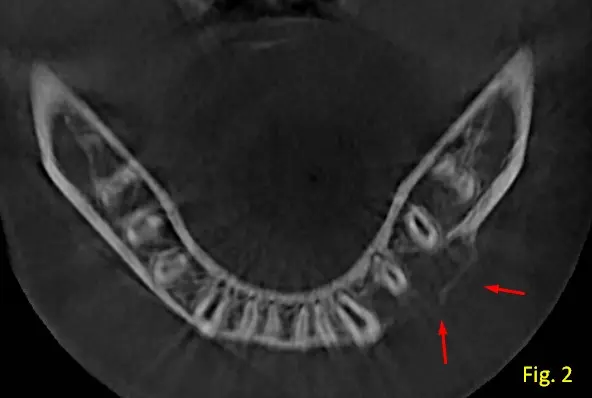

Presenta una tabla ósea en zona de pd 33,34,35 con abombamiento y en alguna zonas muy adelgazada, con posible ausencia de la misma (ver figura 2, vista axial).